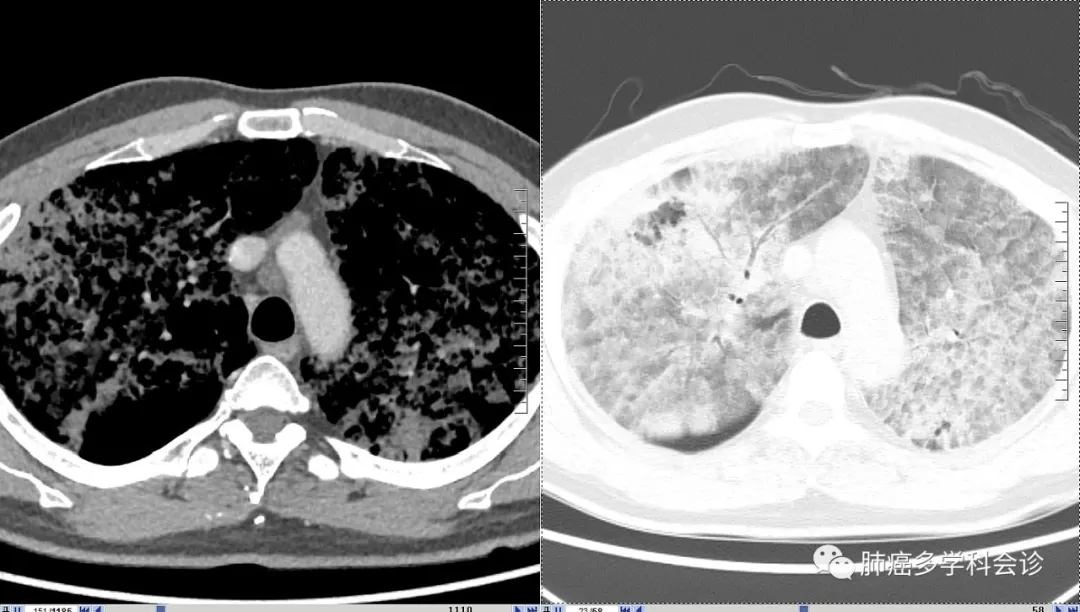

这种 CT影像符合过去的“肺泡细胞癌”特征,大量白色稀薄泡沫痰也是其特征之一,最初的病理也考虑这一诊断。但再次活检的病理诊断:粘液腺癌,并发生了 K-ras基因突变。

患者周围血白细胞、CRP和降钙素原都不高,也没有发热,与几年前肺部CT影像特征较一致,只是肿瘤组织占领的范围明显扩大,能够排除肺部感染。临床上需要与肺部的特殊感染做鉴别。

该患者的疾病进展相对缓慢,很可能更早就发病,直到4年前才引起症状,机体逐渐适应了肺被肿瘤组织占领、缺氧的状态,长期缺氧致使 Hb高达173g/L,红细胞压积高于正常范围上限。血压升高也可能与缺氧有一定关系(类似于高原性高血压)。